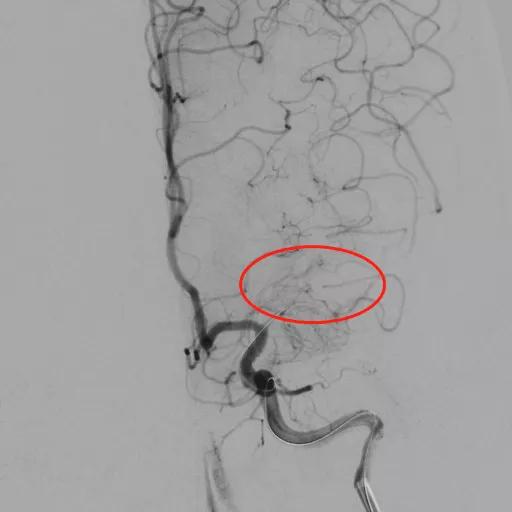

经股动脉或者桡动脉穿刺,置入动脉鞘管;经动脉鞘管将指引导管置入病变血管;将微导丝通过颅内动脉狭窄部位远端血管,使用球囊导管进行预扩张;根据血管大小选择相应的支架推送到狭窄部位并释放。

支架成形术前,左侧大脑中动脉闭塞